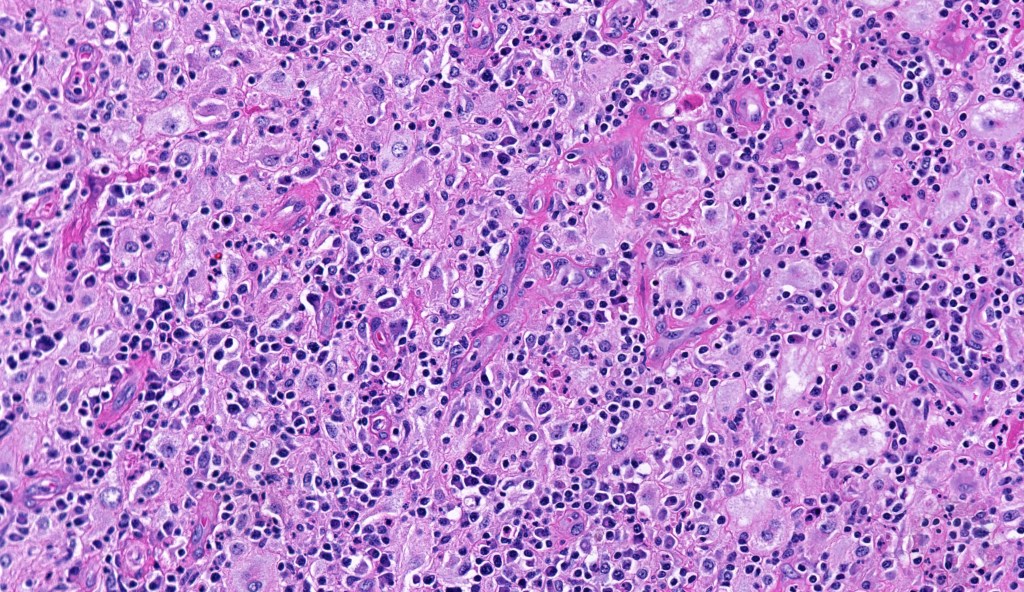

•Histiocytes are large with irregular borders and abundant cytoplasm

• Vesicular nuclei with a prominent nucleoli

•Emperipolesis of lymphocytes, plasma cells & neutrophils

•Background population of lymphocytes, plasma cells, neutrophils, eosinophils & variable numbers of xanthoma cells

•Lymphoid follicles with germinal centers sometimes present